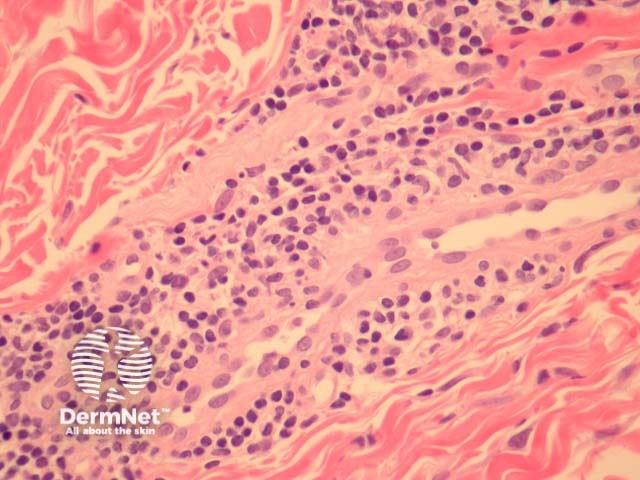

In perniosis, sections show acral skin with a dense superficial and deep lymphocytic infiltrate (figure 1). Subepidermal oedema may be marked. The characteristic feature is lymphocytic perivascular infiltrate within the dermis and sometimes extending to the subcutis (figures 2, 3). This is thought by some authors to represent the one true “lymphocytic vasculitis”, as there may be well established fibrinoid change and thrombosis can occur. There may be numerous eosinophils in early lesions (figure 4).

Figure 1

Figure 2